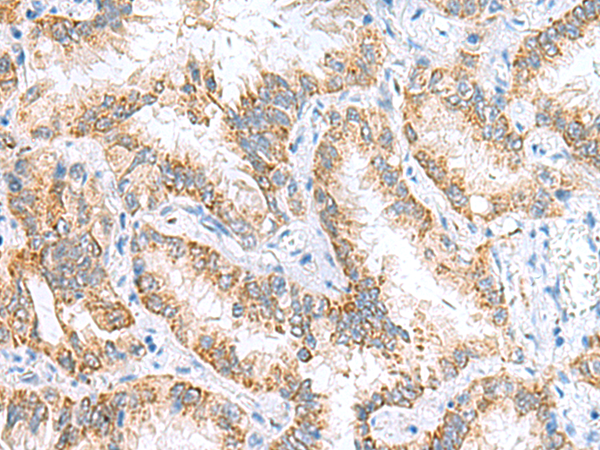

分类: 科研抗体货号: P10218别名: MSL1v2; C2orf67应用: IHC反应种属: Human, Mouse